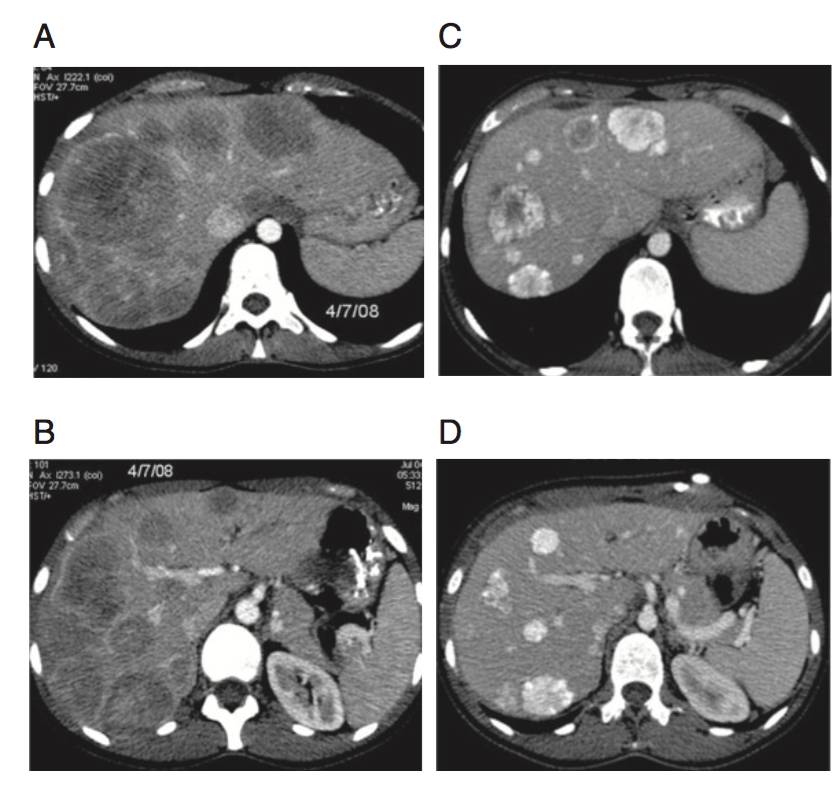

(A&B)上腹部CT显示多发、不可切除、同时性肝转移,原发灶来源自乙状结肠。

(C&D)在一线FOLFIRI方案9周期化疗后,复查CT评价为影像学略缓解(缩小幅度明显降低)。行乙状结肠癌切除术,术中留置HAI导管。

(E&F)4周期三药方案HAI+西妥昔单抗治疗后,复查CT评价为显著影像学缓解。行分期肝切除术。

(G&H)术后3年复查未见肿瘤复发,PS评分=0。